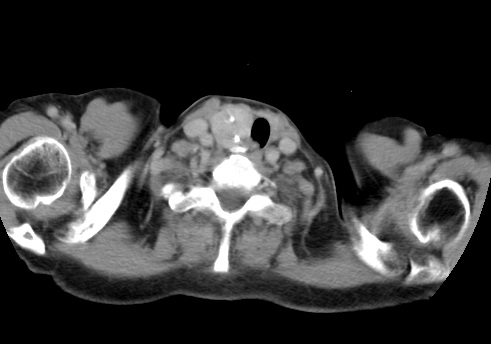

标题: CT23982:女67岁,胸部扫描时发现,甲状腺瘤? [打印本页]

标题: CT23982:女67岁,胸部扫描时发现,甲状腺瘤?

右侧甲状腺腺瘤!支持!不排除甲状腺癌可能!建议手术切除!

右侧甲状腺占位性病变,性质待定(甲状腺腺瘤?);建议:必要时行进一步检查。

右侧甲状腺占位性病变,性质待定(甲状腺腺瘤?);建议穿刺活检。

右侧甲状腺占位性病变,甲状腺腺瘤可能,建议穿刺活检。